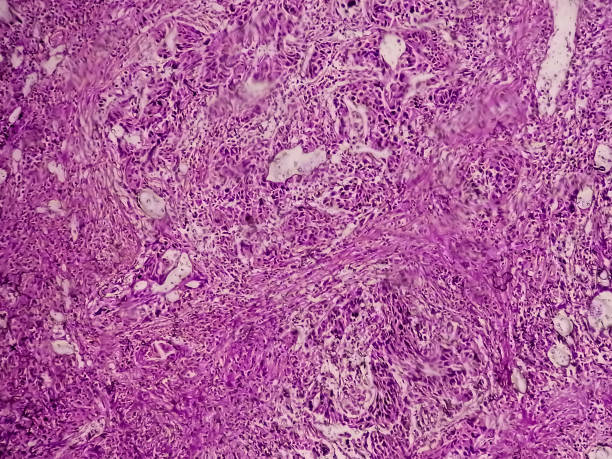

방광암은 초기에 증상이 뚜렷하지 않아서, 발견되기 전까지 오랜 기간 동안 증상이 없을 수 있습니다. 이로 인해 진단이 늦어져 치료가 어려워질 수 있습니다. 그러므로, 방광암의 초기증상을 잘 알고 있어야 증상이 나타났을 때 빠르게 대처할 수 있으며, 조기 발견과 치료로 인한 예후 개선 가능성이 큽니다. 또한 방광암은 흡연, 화학 물질 노출, 방광염 등의 위험 요인에 노출되면 발생할 가능성이 높습니다. 따라서 위험 요인에 노출되는 직업이나 환경에서 근무하는 사람들은 방광암에 대한 예방과 조기 발견에 더욱 신경써야 합니다.

방광암의 초기증상 중 하나로 소변에 섞인 혈뇨나 핏물이 나오는 경우가 있습니다. 방광 내부의 종양이 소변에 혈관을 침범하여 혈뇨가 발생할 수 있습니다. 소변에 섞인 혈뇨나 핏물이 나오는 경우에는 의사를 찾아 상세한 검진을 받아야 합니다. 이러한 혈뇨나 핏물이 지속되는 경우 진단과 치료를 위해 빠른 시일 내에 의료 전문가의 조언을 받아야 합니다.